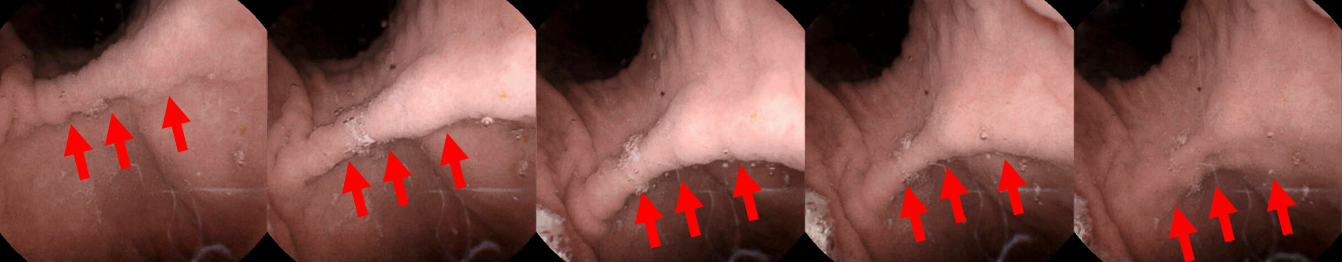

Refer to caption

Fig. 1: A video frame sequence of gastric contraction wave captured by MCCE. The contraction wave has spatial features within single frames and temporal features across the frame sequence. The sequence is temporally undersampled by eight for better visualization. The red arrows highlight the contraction wave.

The median gastric examination and transit time using MCCE takes around one hour in clinical applications [7]. An example of gastric contraction wave captured by MCCE is shown in Figure 1. For evaluating gastric motility, consistent attention from doctors and experts are required during the whole examination process. There is a need to develop computer vision-based algorithms for analyzing MCCE video sequences and evaluating gastric motility. During the gastric examination, the MCCE capsules have five controlled degrees of freedom (two rotational and three translational) and one uncontrolled degree of freedom (rotation along the long axis of the capsule). Action recognition from moving cameras poses significant challenges [8]. To mitigate the sudden movement of the MCCE capsule camera in the six degrees of freedom, we develop a camera motion detector (CMD) for processing MCCE video sequences. We evaluate gastric motility from two aspects. First, we detect the presence of contraction waves in MCCE video sequences. Then, we measure the period of contraction waves. We use convolutional neural network (CNN) and long short-term memory (LSTM) for contraction wave detection. Moreover, we develop a periodical detector that measures the periods of human gastric contraction waves.